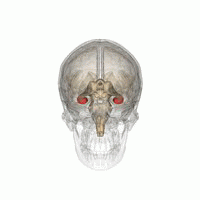

海马体(Hippocampus)又名海马回、海马区,是位于脑颞叶内的一个部位的名称,人有两个海马,分别位于左右脑半球。它是组成大脑边缘系统的一部分,担当着关于记忆以及空间定位的作用。名字来源于这个部位的弯曲形状貌似海马。 在阿兹海默病中,海马体是首先受到损伤的区域:表现症状为记忆力衰退以及方向知觉的丧失。大脑缺氧(缺氧症)以及脑炎等也可导致海马损伤。 在动物解剖中,海马体属于脑的演化过程中最古老的一部分。来源于旧皮质的海马体在灵长类以及海洋生物中的鲸类中尤为明显。虽然如此,与进化树上相对年轻的大脑皮层相比,灵长类动物尤其是人类的海马体在端脑中只占很小的比例。相对新皮质的发展,海马体的增长在灵长类动物中的重要作用是使得其脑容量显著增长。

尽管关于海马与其向邻近的大脑皮层的表述尚缺乏一致的观点,通常情况下术语上的“海马结构”指的是齿状回,CA1-CA3部位(或CA4,常称为hilus区并被认为是齿状回的一部分),以及脑下脚(另见阿蒙神之角)。CA1与CA3部位构成严格意义上的海马。